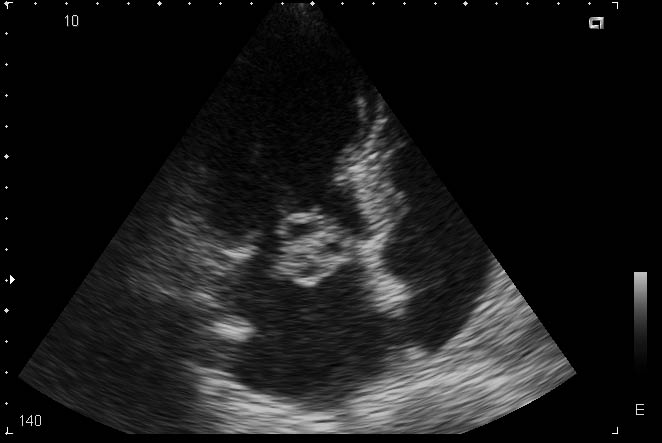

ПРИ ПЛАНОВОМ ОБСЛЕДОВАНИИ ПОСЛЕ ПЕРЕНЕСЕННОГО МЕЛКООЧАГОВОГО ИНФАРКТА МИОКАРДА ПОЛУЧИЛАСЬ ТАКАЯ КАРТИНКА. КАК ДУМАЕТЕ, ЧТО ЭТО МОЖЕТ БЫТЬ. И ТАКТИКА.

КЛИНИЧЕСКАЯ КАРТИНА СЛЕДУЮЩАЯ: ЛИХОРАДКА В ТЕЧЕНИЕ 4Х МЕСЯЦЕВ, ЛЕЧИЛАСЬ В ИНФЕКЦИОННОЙ БОЛЬНИЦЕ С ДИАГНОЗОМ ЛИХОРАДКА НЕЯСНОГО ГЕНЕЗА, АНЕМИЯ СРЕДНЕЙ СТЕПЕНИ, АСТЕНИЗАЦИЯ.

Наиболее вероятен бактериальный септический эндокардит с поражением ПС МК, абсцесс створки?

дело в том, что клапан как-бы и не изменён, может не очень хорошо видно на картинках и ролике, а это образование крепится у основания створки. Просто ни с чем подобным раньше сталкиваться не приходилось, да и в литературе подобных картинок нет. Как вариант, абсцесс тоже рассматривается. Диагноза точного пока нет. Вероятно больную направят в РНПЦ Кардиологии, результат обязательно сообщу.

Следует дифференцировать инфекционный эндокардит и опухоль сердца.

Для инфекционного эндокардита сроком давности 4 мес хотелось бы иметь большую степень поражения митрального клапана в виде его недостаточности (митральная регургитация, дилатация и объемная перегрузка левых отделов сердца).

Для опухоли, которая чаще всего представлена миксомой, не совсем типично место, из которого она исходит.

А клиника может быть сходной. Описан синдом отравления опухолью даже для миксом.

Больше данных в пользу инфекционного эндокардита с абсцессом передней створки митрального клапана. Учитывая анамнез можно предположить, что больной проводилась антибиотикотерапия, поэтому процесс на створке не привел к выраженной митральной недостаточности. В данном случае, мне кажется, необходим динамический ЭхоКГ-контроль на фоне лечения антибиотиками (с учетом диагноза ИЭ).